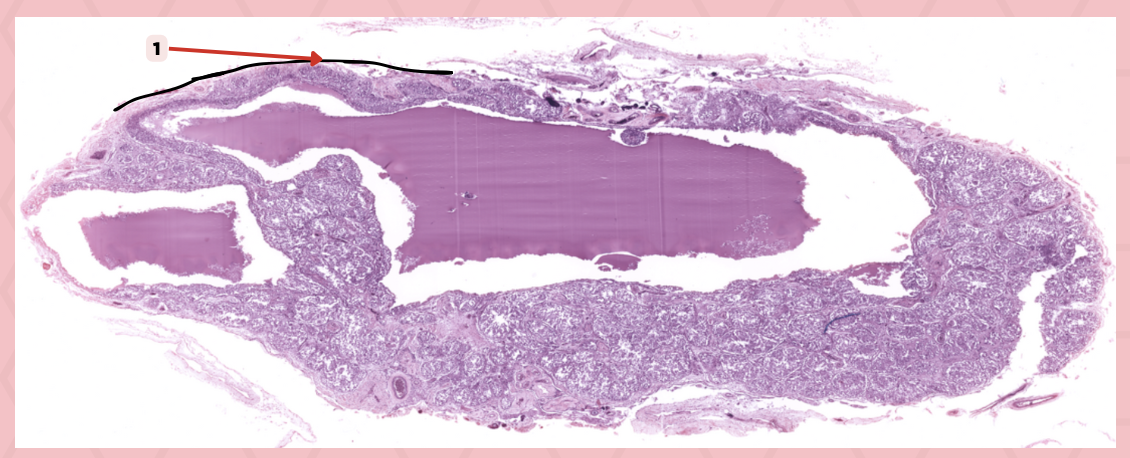

Thyroid-Parathyroid

Identify the specimen.

Thyroid Gland

Identify the structure labeled as 1.

Capsule

Identify the structure labeled as 2 and 4.

Parathyroid Gland

Identify the structure labeled as 3.